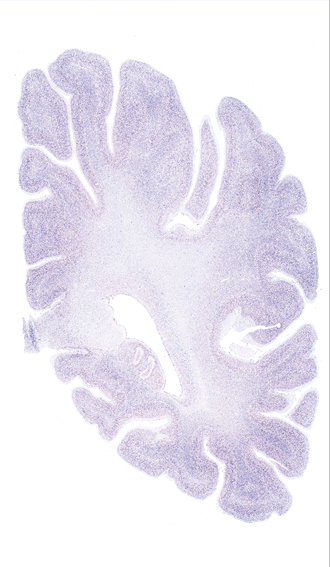

Hi-Resolution Sections · Cells (Nissl Staining) · Virtual Microscopy

Frontal sections (Nissl) from the Atlas Brain:

Slice ID:

r4-0320

Plate NR:

53

Position:

45,4 mm